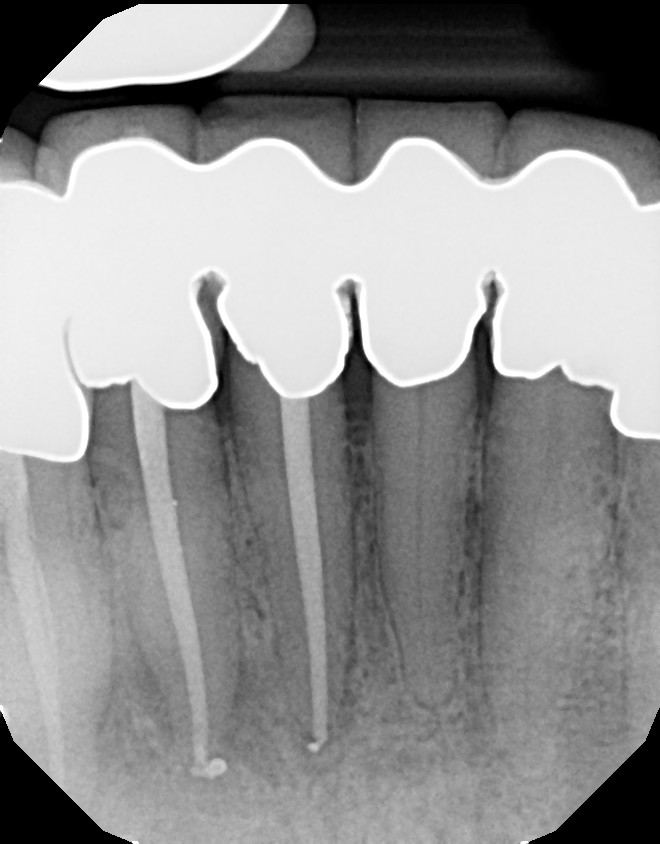

This is a multiple tooth / root issue that developed over time (4-5 years) under crowns where the nerves died and caused infection. After 3 months, bone regeneration (healing) occurred where infection was initially present. Endodontists (root canal specialists) are an important part of dental care for diagnosing and treating root issues.